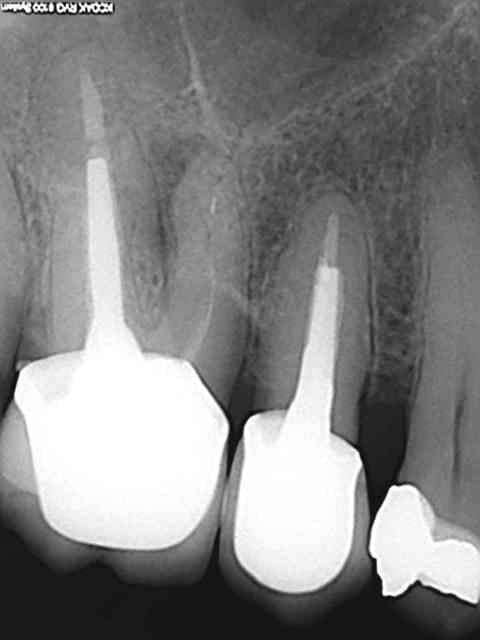

Et puis si une autre pour la route.)))))